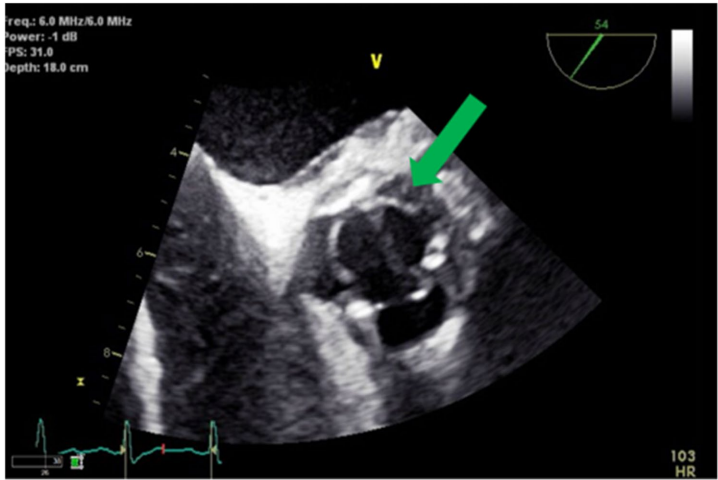

《Cardiovascular Ultrasound》近期报道的一例致命病例凸显了这些挑战的严重性。一名51岁曾有静脉吸毒史和甲氧西林敏感金黄色葡萄球菌(Methicillin-susceptible Staphylococcus aureus, MSSA)心内膜炎病史的男性患者,在接受生物主动脉瓣置换术后再次出现MSSA菌血症。初始TEE检查未发现赘生物或脓肿,患者在接受10天抗生素治疗后出院,并计划每周使用达巴万星(Dalbavancin)进行四次治疗。令人震惊的是,出院仅三天后患者就因发热、精神状态恶化和神经功能缺损再次入院,影像学检查显示大脑、肺脏、脾脏等多器官梗死。尽管重复血培养仍为MSSA阳性,TEE检查再次报告阴性。直到转入四级医疗中心后,TEE才最终发现大型主动脉根部脓肿已侵蚀室间隔膜部,形成左心室至右心房的异常通道——即Gerbode缺损。

紧急TEE检查证实了室间隔完全侵蚀和生物主动脉瓣膜开裂,二维图像清晰显示右心房内大型赘生物和相关的Gerbode缺损。多普勒超声进一步显示主动脉根部感染沿瓣周扩展,室间隔膜部侵蚀入右心房,左心室流出道与右心房之间存在连续性左向右分流,并伴有重度主动脉反流。